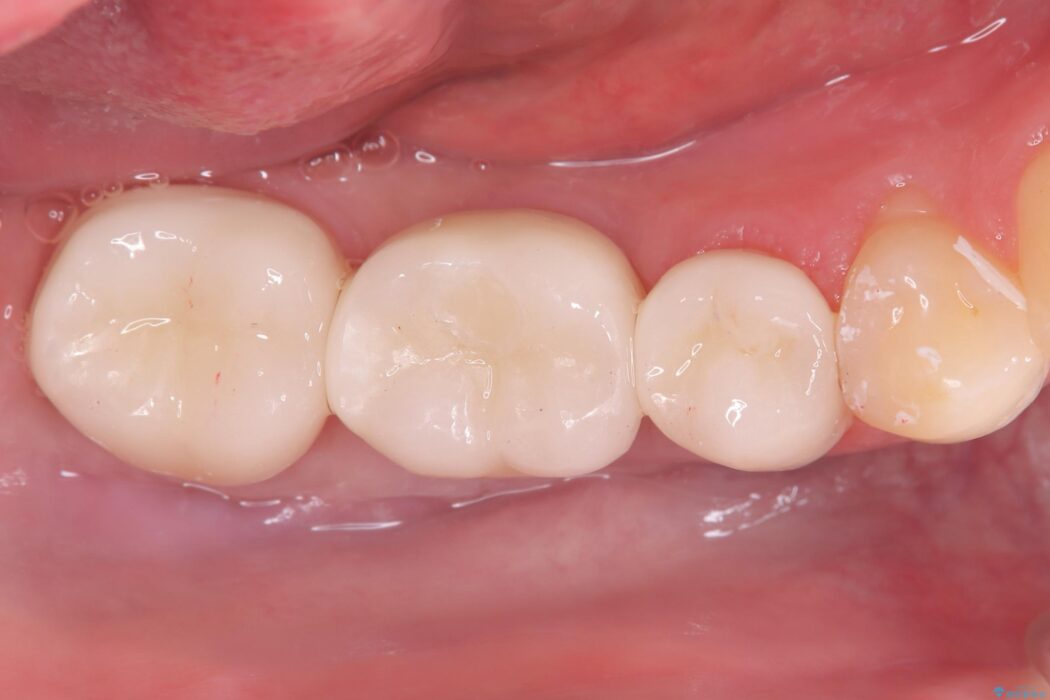

ブリッジを外し、欠損している6番にインプラントを埋入。土台となっていた5番と7番は、セラミッククラウンで修復。

インプラント周囲の歯肉が薄かったため、FGG(遊離歯肉移植術)を行い、長期安定に不可欠な「角化歯肉」を確保しました。

FGG(遊離歯肉移植術)の実施: インプラントを長持ちさせるためには、周囲に硬く動かない「角化歯肉」が必要です。患者様の上あごから丈夫な歯肉を移植するFGGを行うことで、インプラント周囲に十分な厚みと幅のある角化歯肉を形成しました。